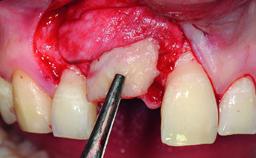

A 32-year-old female Caucasian patient with a compromised maxillary right central incisor was referred to us by a general dentist. Her chief complaints were discomfort and mobility of tooth 11 with unsatisfactory esthetics due to discoloration. The patient reported a previous trauma, some years earlier, as the origin of pathology on the afflicted tooth. Anamnesis was negative for any other dental or periodontal pathology in the remaining dentition. The patient did not take any medication and reported to be a light smoker (5–10 cigs/day). She had high esthetic expectations of her treatment. The extraoral examination revealed a high smile line with full exposure of her maxillary teeth and surrounding soft tissue in the area between the second premolars.

| Bone Augmentation | Horizontal|Simultaneous|Staged |

| Augmentation Materials | Autogenous chips|Xenogenous|Membrane |

| Bone Volume | Deficient horizontally, requiring prior grafting |